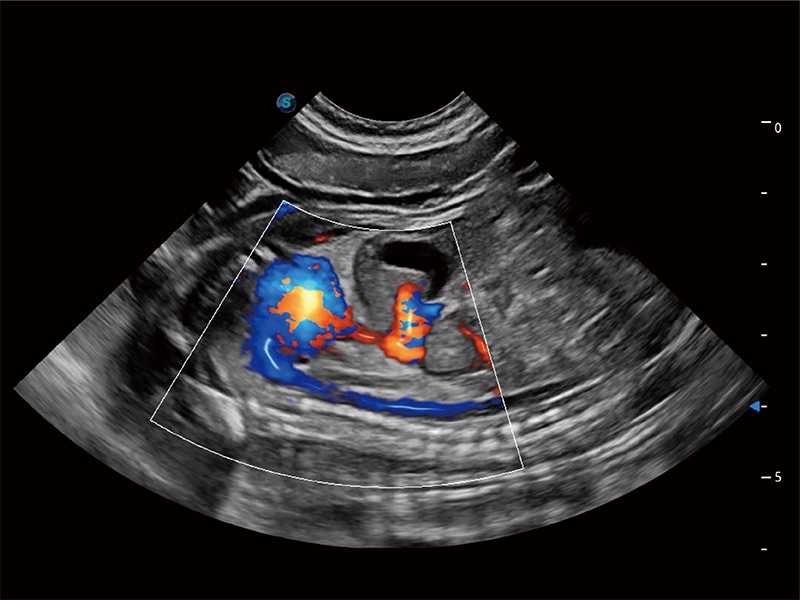

(犬)胎儿主动脉弓立体血流

(犬)四腔心MQA

(犬)二腔心血流

得心应手 心脏解决方案

ProPet 80 配备了丰富的心脏探头群、先进的成像技术和专业的心脏测量工具,可帮助动物医生为不同体型和生理结构的动物提供心脏和心肌功能的全面评估。

• TDI 组织多普勒成像

实时用颜色表示心肌组织运动,观察和定量组织的运动情況,对快速检测与评估心肌的灌注和活性、电传导及心肌收缩和舒张功能等均能提供重要的诊断信息。